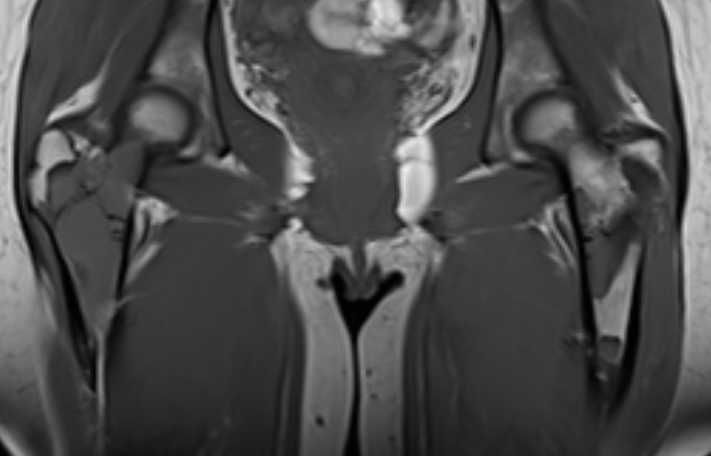

MRI

Low signal intensity T1 / High signal intensity T2